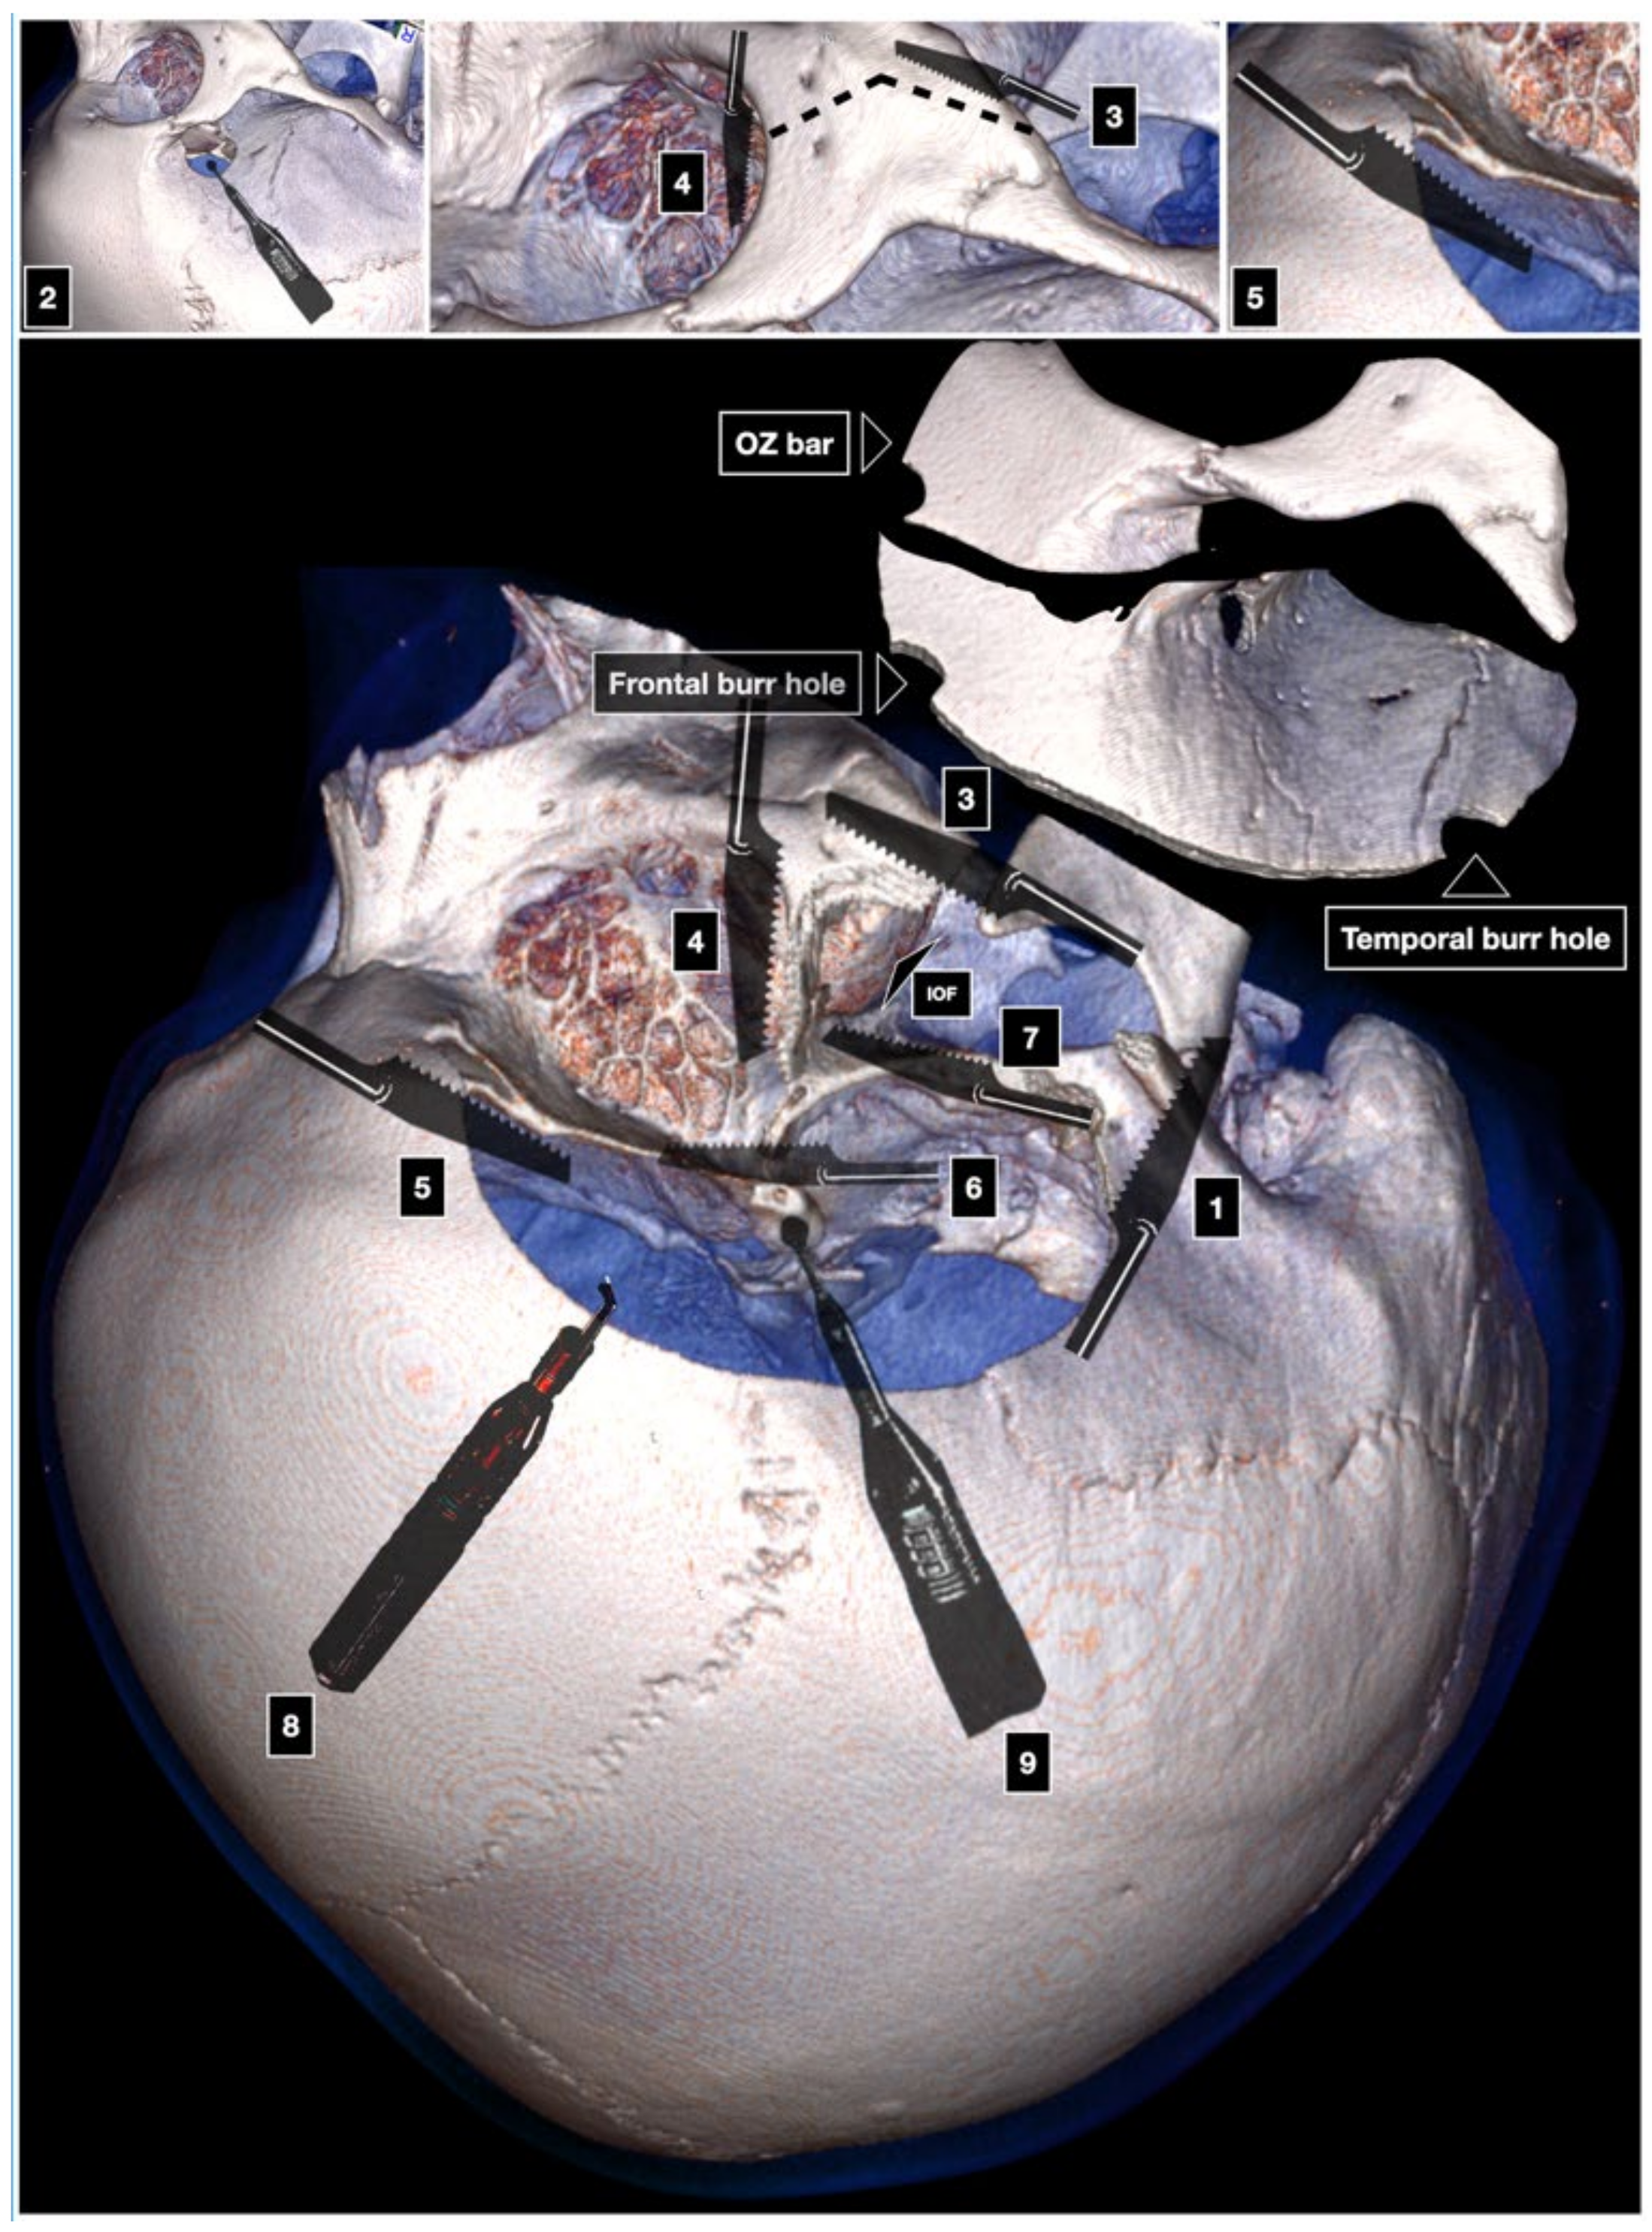

- Orbitozygomatic Craniotomy (Zabramski Technique)